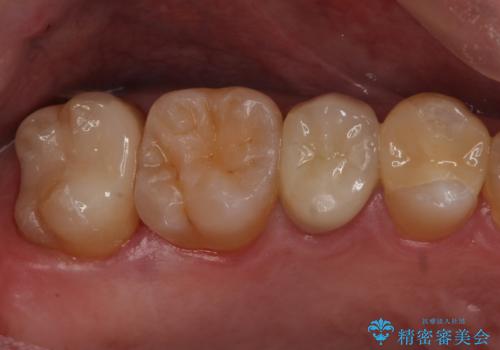

セラミック治療 → セラミックインレー

歯と歯の間によくものが詰まる。。セラミック治療

銀の詰め物を白い物にしたい